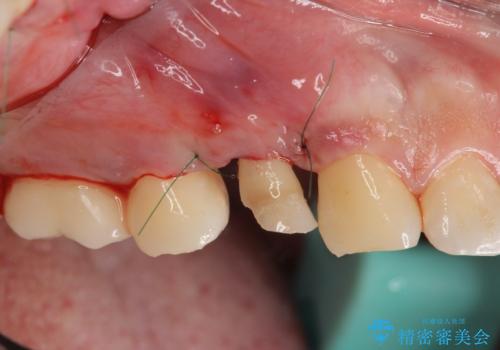

今回は虫歯の深いところが歯茎のラインにくるまで部分矯正で引っ張り出し、適合の良いかぶせ物を装着しました。

虫歯を取り切った後は、歯を引きあげたことで一緒に上がってきてしまった骨をならしていきます。

その後ラバーダムをして根っこの治療をし、被せ物を被せて治療終了となりました。